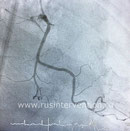

Коронарография - "золотой стандарт" в кардиологии при ишемической болезни сердца.

Коронарография (или коронарная ангиография) – метод диагностики состояния коронарного русла. Она позволяет определить локализацию и степень сужения коронарных артерий.